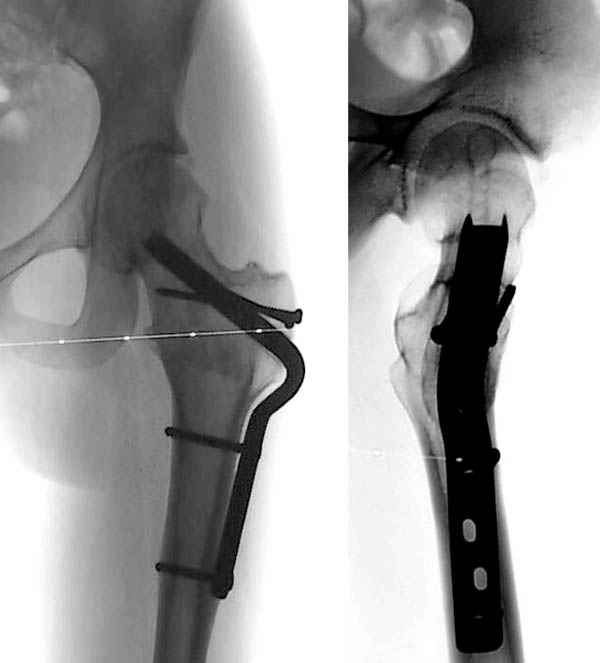

Здесь представлен один из случаев остеотомии на шейке после остаточного явления юношеского эпифизиолиза из Flip Trochanteric доступа.

На основе этой работы был предложен анатомичекий доступ к проксимальному отделу бедра, так называемый Digastric или Flip Trochanteric Approach.

Доступ удобен при "circumcision osteoplasty" при импинжменте, при переломах головки, лабральной патологии, при удалении медиальных остеофитов из дна вертлужной впадины, а также при коррекции проксимальной части бедра.

Характерным отличием является то, что Vastus Lateralis and Gluteus Medius остаются прикрепленным к кости. Остеотомия трохантера на уровне прикрепления мышц, потом капсулотомию делают в форме Z вместо Т, что дает лучший обзор. При вывихе головки артерия циркумфлекс защищается сухожилием обтуратора интернус.